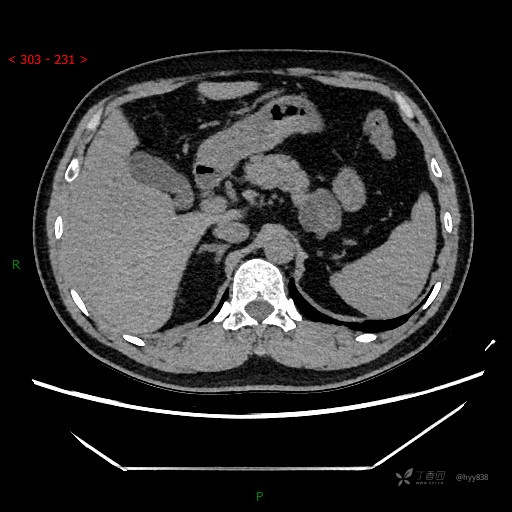

静脉期